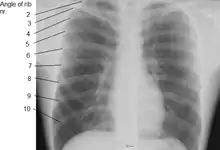

![]() صورة بالأشعة السينية للصدر توضح التشريح الداخلي للقفص الصدري، الرئتين و القلب، وكذلك الحدود الصدرية السفلية المكونة من الحجاب الحاجز. | |